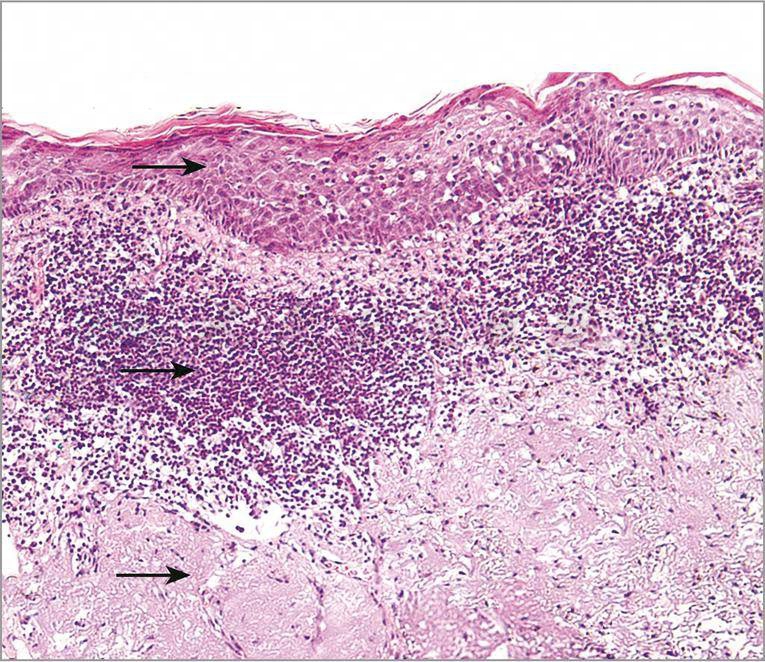

病理表现为表皮角化过度间有角化不全,棘层肥厚,轻度乳头瘤样增生,表皮突不规则下延。表皮细胞排列紊乱,细胞大小不等,形态不一(图1)。细胞核深染,大小不等,形状不规则,核分裂象常见。表皮中部可见角化不良细胞。真皮浅层胶原纤维嗜碱性变性,血管扩张,血管周围以淋巴及组织细胞为主的炎症浸润,还可见浆细胞和多核细胞(图2)。

图2 光化性唇炎:继前图示

表皮细胞异型性(上箭头),真皮混合炎细胞浸润(中箭头)伴有日光性损伤改变(下箭头)